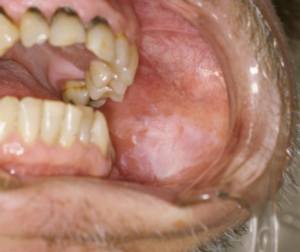

口腔白板症

口腔白板症は、舌や頬の粘膜に白い斑が現れる病気です。

前がん病変として知られていますが、多くは痛みがないため気づきにくく、歯科医院での診察で見つかることが少なくありません。

原因には、合わないかぶせ物や義歯などの慢性的な刺激、喫煙や飲酒、加齢に伴う粘膜の抵抗力低下が関わると考えられています。

白板症のすべてががんになるわけではありませんが、一部は悪性に変化する可能性があるため、白板が厚みを増したり、びらんや潰瘍を伴ったりする場合は注意が必要です。